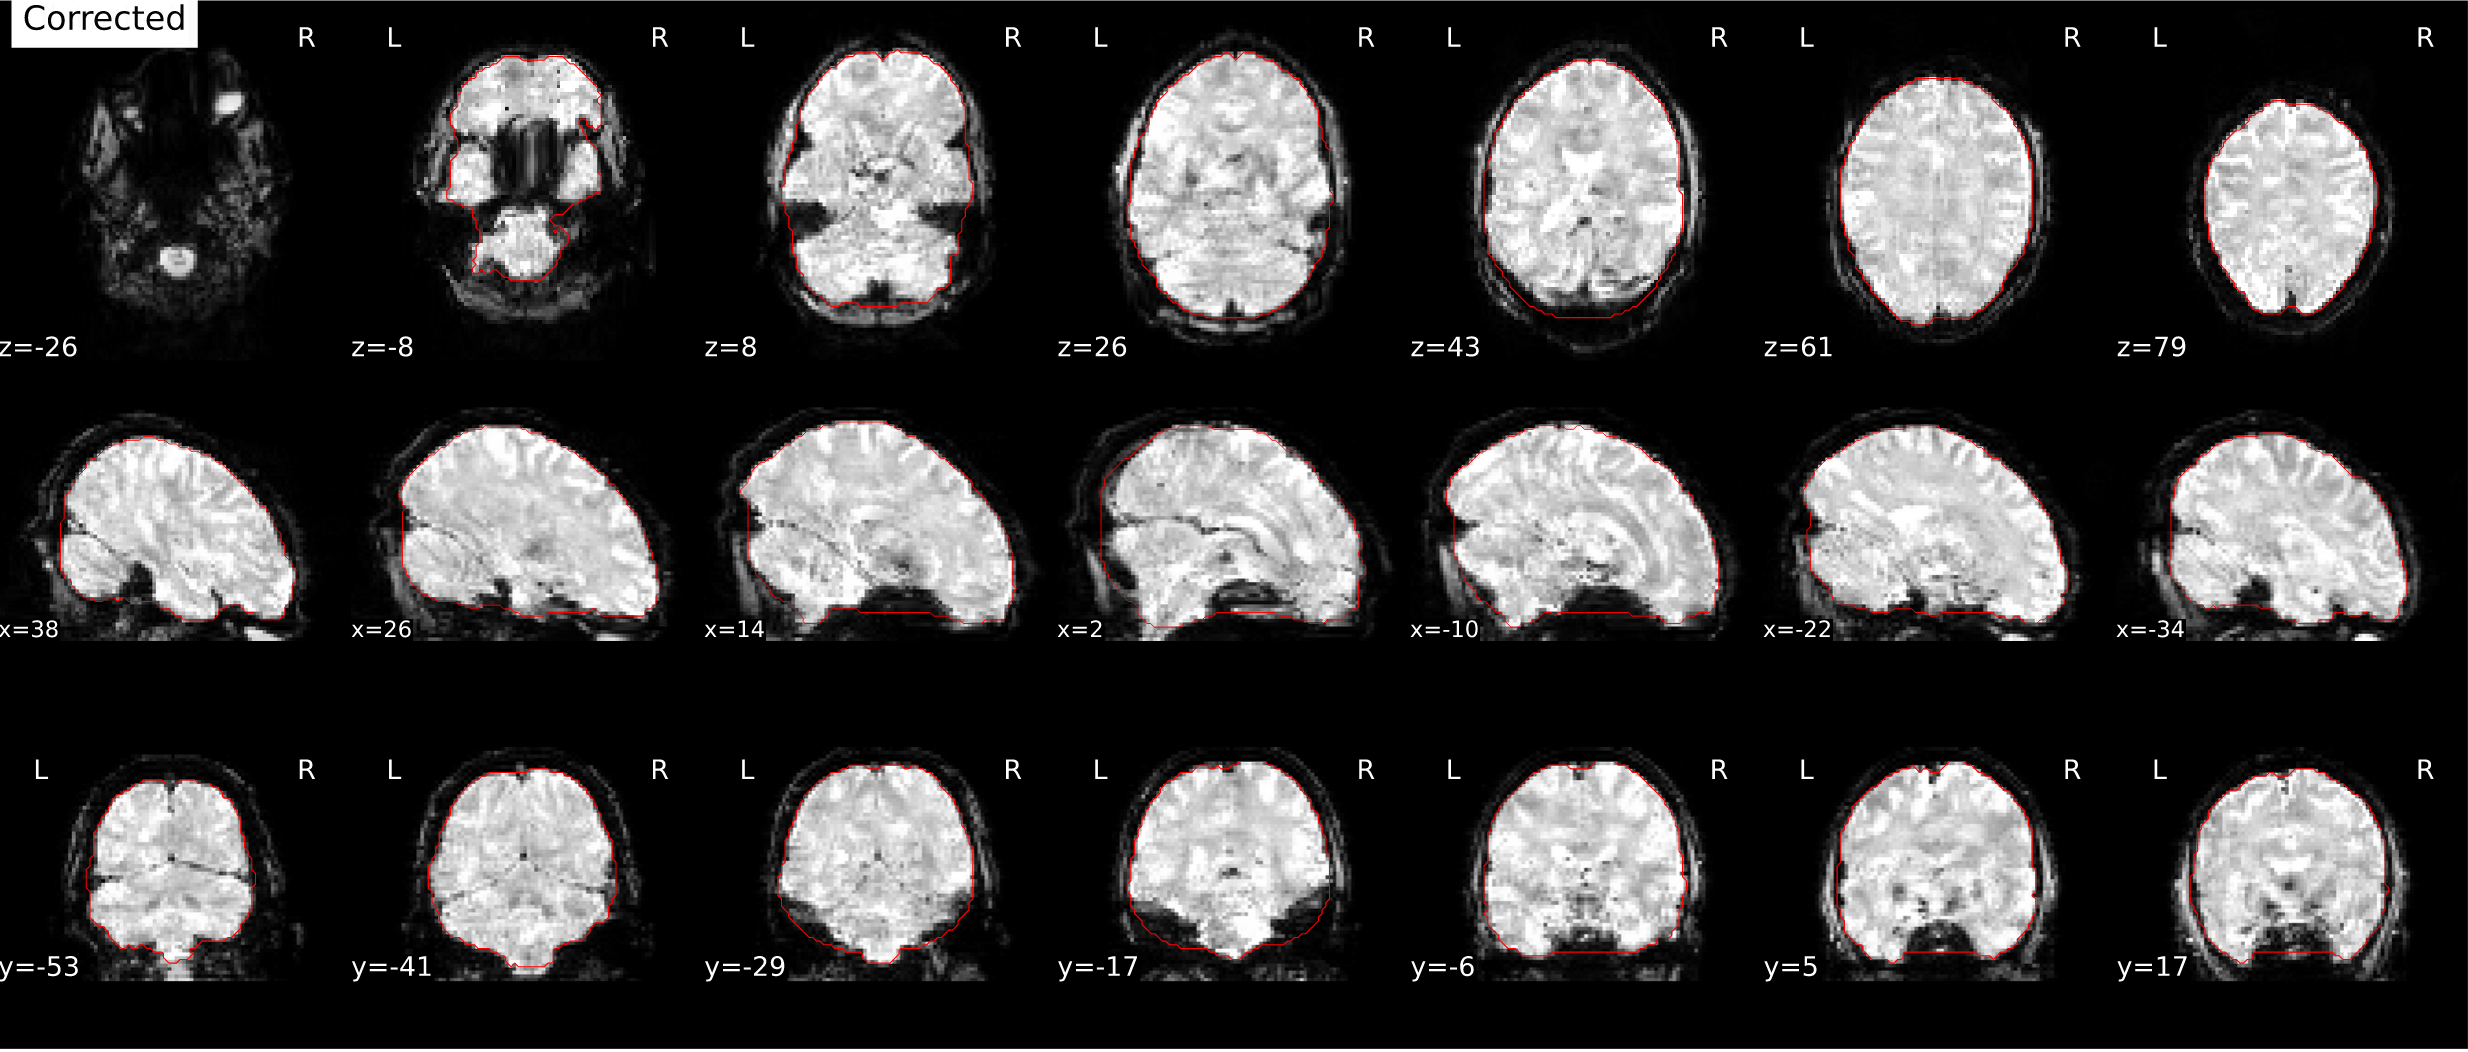

Allows SimpleBeforeAfter reports to rotate images with respect to the cardinal axes. This is motivated in the context of SDC correction, to give a clearer look at the distortions.

Screen Shot 2021-08-31 at 3 43 06 PM

Screen Shot 2021-08-31 at 3 43 15 PM